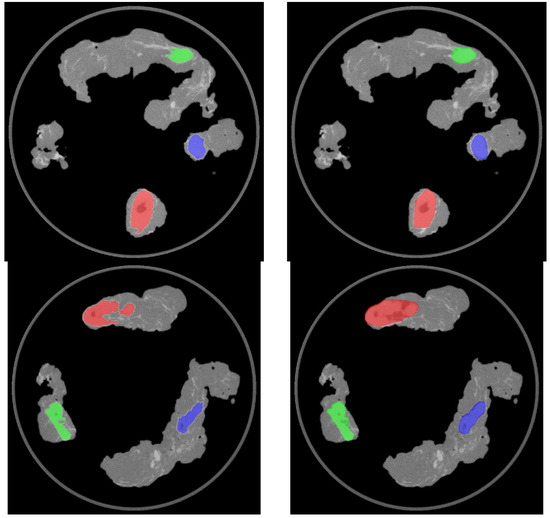

The complete model schema for the automatic nodal segmentation of the 68Ga-PSMA-11 PET/CT specimen images is presented in Figure 3.

Figure 3. Model schema for the automatic CT-based nodal segmentation and PET semi-quantification of 68Ga-PSMA-11 PET/CT specimen images.

Figure 4. Axial images showing the outcome of the automatic (left) and manual (right) segmentation of the 68Ga-PSMA-11 PET/CT nodal specimen images. Top row: left pelvic lymph nodes. Bottom row: right pelvic lymph nodes.